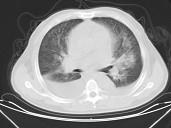

男,32岁,CT图像如图,最可能的诊断为 ( )A.肺水肿并双侧胸腔积液B.周围型肺癌C.肺动静脉瘘D.肺错构瘤E.炎性假瘤

问题 男,32岁,CT图像如图,最可能的诊断为 ( )

选项 A.肺水肿并双侧胸腔积液 B.周围型肺癌 C.肺动静脉瘘 D.肺错构瘤 E.炎性假瘤

答案 A